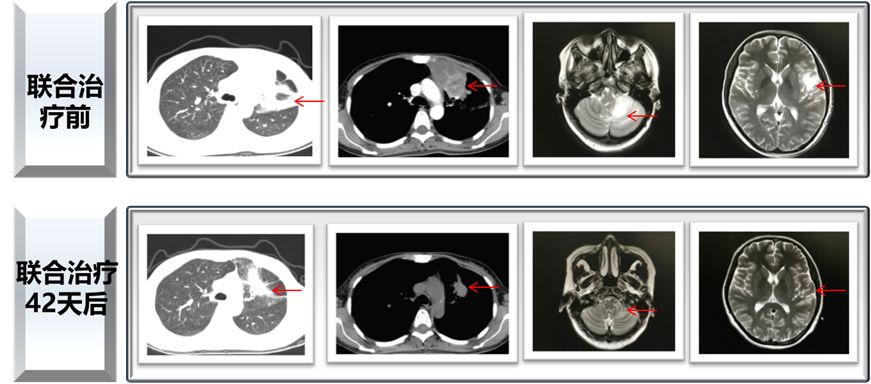

患者在使用奥希替尼耐药后,基因检测发现存在EGFR敏感突变19del,同时存在有MET扩增( ),但不存在T790M突变。基因检测的结果提示一代TKI联合克唑替尼可能会有效果,于是患者在2017年2月7日开始使用一代TKI联合克唑替尼进行治疗,联合治疗42天后,患者的影像学结果有了明显的好转!